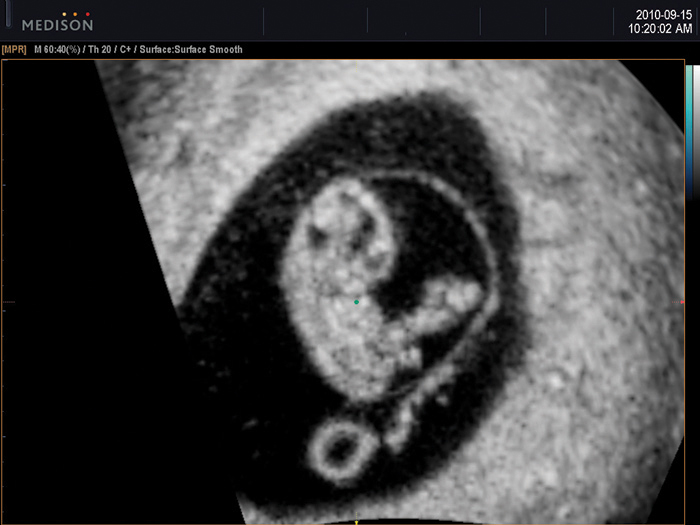

8 hetes magzat képe a coronalis síkban 2D módban8 hetes magzat képe coronalis síkban HD Volume Imaging módban

HDVI™ is based on non stationary adaptive filtering resulting in removal of unwanted speckle and noise whilst increasing visualization of edges and small structures in volume data. HDVI™ uses a 3D processing algorithm that is based on 3D matrix processing of volume data.

The essential feature of this 3D processing algorithm is matrix image processing which allows more accurate rendered information calculated from the voxel data of the acquired volume data.

By using this calculation method, a clear and improved image is shown in the rendered and multi-planar views.

HD Volume Imaging™ (HDVI™) removes artifacts and incorporates a speckle reduction filter without compromising details but at the same time emphasizing the edge and structures. Therefore, 3D rendered image and multi-planar view provides an image quality with improved contrast and resolution. According to the result, it shows that the speckle noise of the image with HDVI™ is lower while the edge enhancement are higher, compared to the Original.